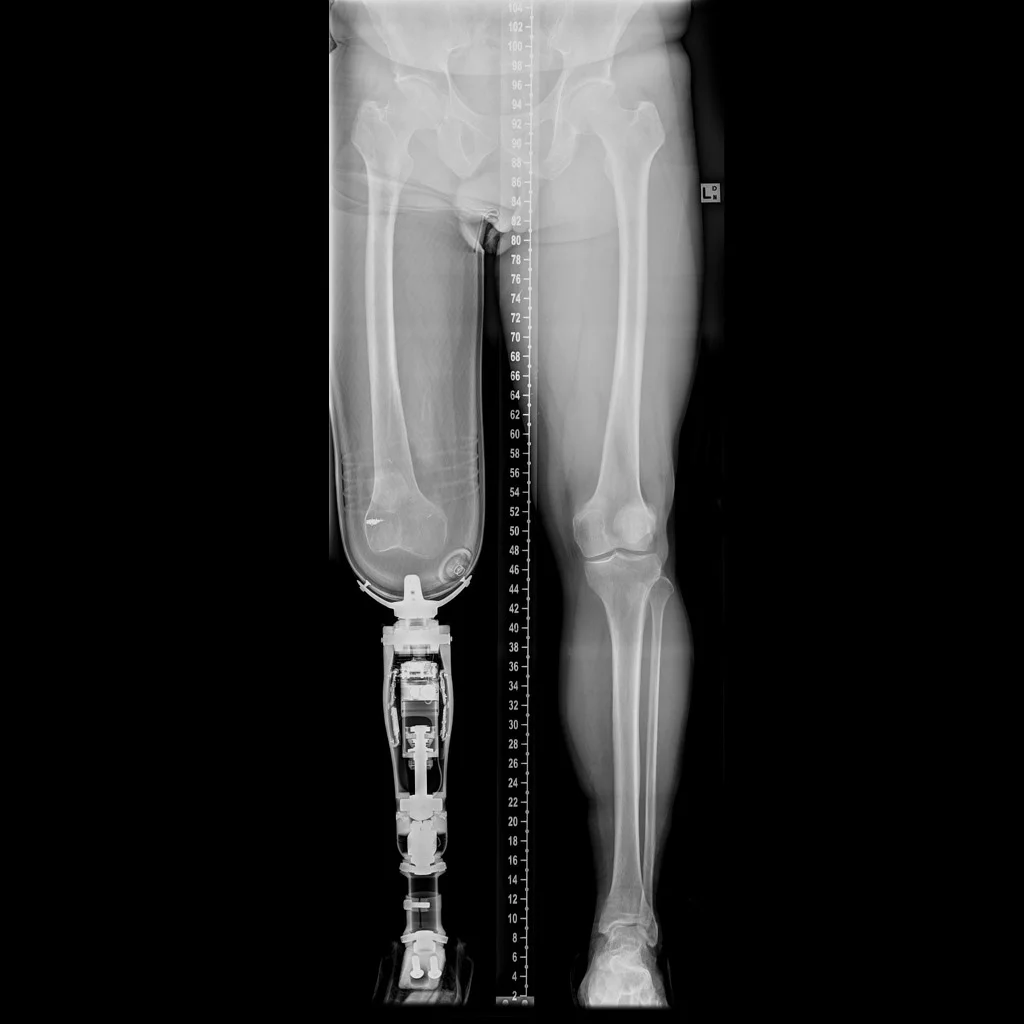

The most current prosthesis, which has to be custom made at a high cost ($3000-$40000) can not fulfill the simplest need of taking shower and cleanning residual limb.

Inspired by the Charles and Ray Eames Leg splint (c.1942 Molded plywood), I wanted to explore the potential of sheet materials and thermal forming techniques to not only solve the problem, but also minimize the cost and add a humanistic touch to the prosthesis.